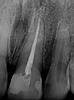

Our Vienna, VA dentists plan treatment using a digital x-ray image of the tooth. We may also recommend a 3-D digital scan of the tooth using CT cone beam technology. This valuable technology provides more information than a two-dimensional x-ray and allows for more precise treatment planning.

When we begin your root canal treatment, we first open a small hole in your tooth to access the root canal. Dr. Sanati and Dr. Sharahm use leading-edge rotary endodontic technology to gently and quickly remove the infected material. Instead of the manual steel files dentists used in the past, rotary endodontics employs an electrically-powered instrument that allows us to perform more efficient and comfortable root canals with a higher success rate for our patients.

When our Tysons dentists have cleared away every trace of the infection, they fill the hollowed-out space with an inert material called gutta-percha and then seal the tooth. Since there is no more blood supplying the tooth, it will become brittle, so we may recommend a dental crown to protect it. If you don't need a dental crown, we will still need to place a filling on the tooth to restore and strengthen it.